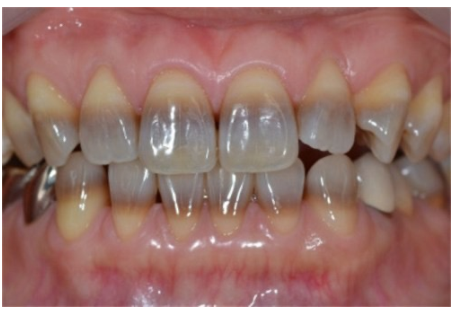

<p>What is this?</p>

What is this?

Tetracycline staining

• Intrinsic yellow-brown stain

• chemically bound to dentin

• most common in children under 8yo or if drug was taken during pregnancy